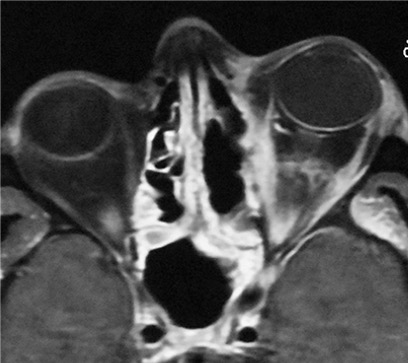

Orbital Surgery

Orbital conditions can cause eye bulging, double vision, pain, swelling or even lumps around the eye and may require imaging and specialised treatment. Orbital surgery demands expertise around critical nerves, muscles and most importantly the eyeball.

Thyroid Eye Disease management

TED can cause prominent eyes, eyelid retraction, dryness, swelling, and double vision – and in severe cases can threaten vision. Treatment is staged and highly complex: medical control first, and surgery only when needed for safety, function, and final refinement.